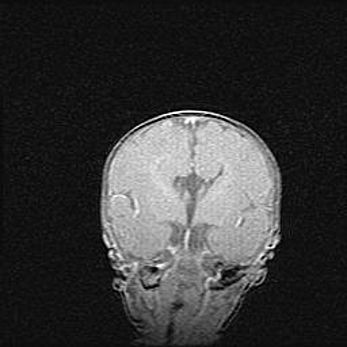

Множественные кисты обоих полушарий головного мозга, наибольшая из них в правой затылочной области. Ассиметричная атрофическая гидроцефалия.

Возраст: 7 месяцев

Вес: 5660 г

Пол: мужской

Окружность головы: 41,5 см

Срок гестации: 28-29 недель

Кисты головного мозга развиваются в результате многоочаговых некрозов вещества мозга и возникают вследствие перенесенной перинатальной инфекции, менингитов, энцефалитов, асфиксии, родовой травмы, расстройств мозгового кровообращения различного генеза. Образованию кист в веществе головного мозга плодов и новорожденных способствуют такие факторы, как высокое содержание в нем воды, недостаточная (или отсутствие) миелинизация и слабая астроглиальная реакция на повреждение.

Кисты могут сочетаться с гидроцефалией и другими поражениями головного мозга.